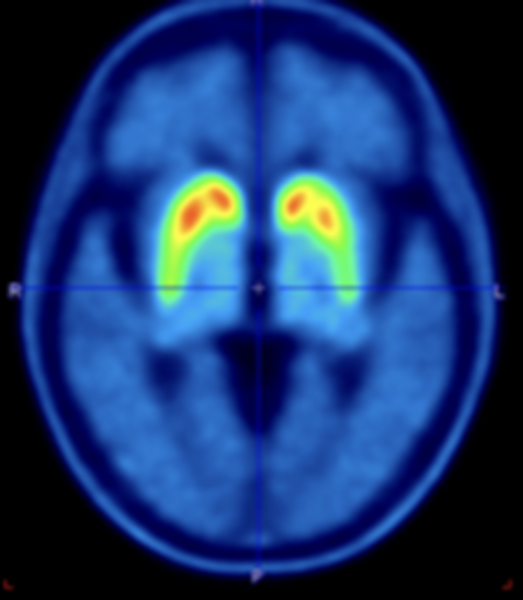

PET/CT scanning of the brain

Participants receive an injection with a small dose of the tracer [18F]PE2I. Subsequently, a PET/CT scan of the head is performed. The tracer measures the amount of functioning dopamine cells in the brain. The dopamine system is damaged in all patients with PD, but the symmetry and the progression of the damage might be different depending on the subtype of PD.

[18F]PE2I PET of the brain

Participants are injected with a small dose of [18F]PE2I. Thirty minutes later, a PET/CT of the head is performed. [18F]PE2I measures the dopamine system in the brain. The dopamine system is damaged in all patients with PD, but the degree of asymmetry and the progression of the damage might be different depending on the subtype of PD.